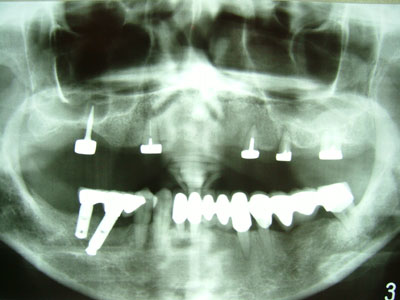

GIII: #17- GIII, #13- GI, #23- GI, #25- GIII, #27- GII). From panoramic film

it shows bone absorption around all maxillary tooth roots more or less.

fig. 05: pre-treatment panoramic film, taken in April. 21. 2005

fig. 18: post-treatment panoramic film, taken in May. 5. 2005

fig. 34: The panoramic film taken in Aug. 4. 2006 shows the bone around the

maxillary roots stops getting worse. Moreover, the bone around the

mini-implant is getting denser then it was 14 months ago (fig.18) which

indicates this mini-implant is going to have a stable future in the oral

cavity and ensures the U-shaped maxillary denture base can be maintained.